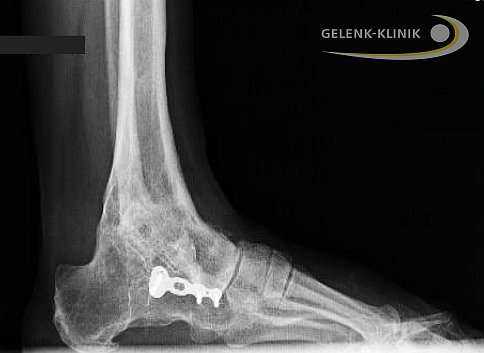

Артродез помогает восстановить безболезненность и потерянную подвижность. Данное вмешательство требует использования специальных винтов и интрамедуллярных гвоздей. Они фиксируют сустав до полной оссификации. © Gelenk-Klinik

Обездвиживание голеностопного сустава проводится под общим наркозом. Иногда используется и местная анестезия. Перед началом остеосинтеза, голеностоп освобождают от суставного хряща, то есть удаляют скользящий слой между суставными элементами голеностопа. Лишь после этой процедуры образуется прямой контакт между большеберцовой и таранной костями.

Прочное важное для остеосинтеза костное соединение, закрепляется при помощи винтов либо пластин. Артроскопические вмешательства подразумевают лишь микроскопические разрезы на коже. Сохранение мягких тканей является является важным элементов в таком лечении: только при низком рубцевании, в будущем возможно эндопротезирование.

Артродез голеностопного сустава проводится и при использовании интрамедуллярных гвоздей, которые соединяют большеберцовую кость с таранной и пяточной. Артроз нижнего голеностопа и тяжелые травмы пяточной кости требуют проведения данной методики. Применение интрамедуллярных гвоздей для обездвиживания голеностопа приводит ещё и обездвиживанию сустава между пяточной и таранной костью. © Gelenk-Klinik